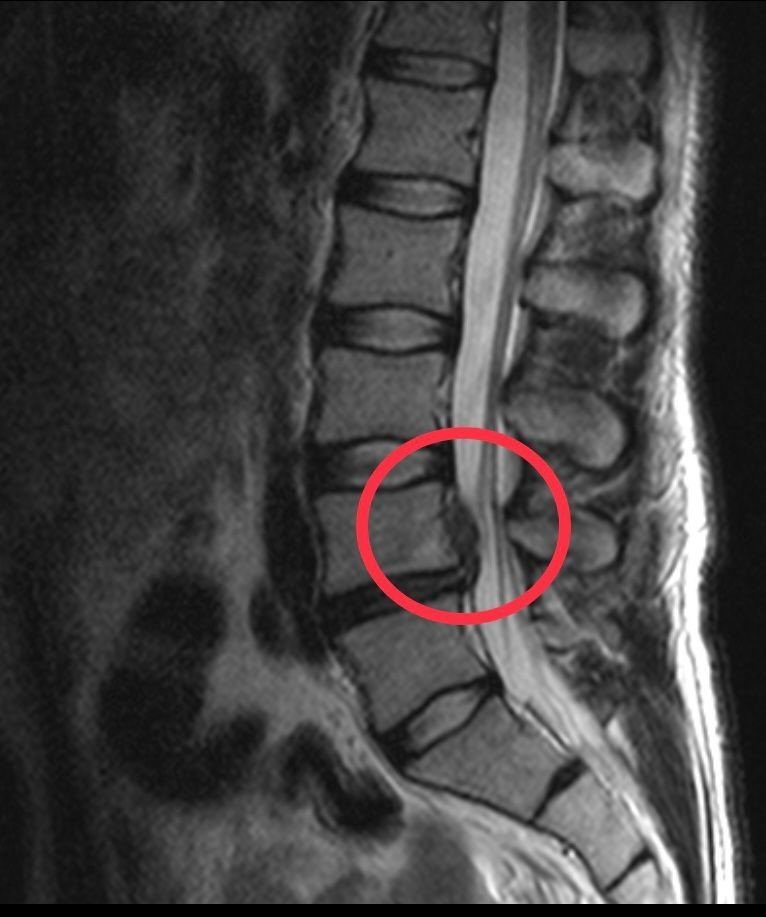

Düzce Üniversitesi Hastanesi'nin başarısı ülke sınırını aştı. 23 yıldır İskoçya'da yaşayan ve orada kuaför olan 40 yaşındaki Yasin Emre Meydan çektiği ağrılardan Düzce'de kurtuldu. Yaşadığı İskoçya'da rahatsızlığına bir türü çözüm bulamayınca tatil için geldiği memleketi Düzce'de, Düzce Üniversitesi Hastanesi'nde yapılan tetkikte bel fıtığı olduğu tanısı konuldu. Düzce Üniversitesi Tıp Fakültesi Hastanesi Beyin ve Sinir Cerrahisi Anabilim Dalı Doç. Dr. Cengiz Tuncer'in yaptığı başarılı ameliyat ile Yasin Emre Meydan sağlığına kavuştu.

Doç. Dr. Cengiz Tuncer de "İskoçya'dan bel fıtığı tanısı ile ameliyat olmak için Düzce'mize gelen hastamızın operasyonunu başarı ile tamamladık" dedi.